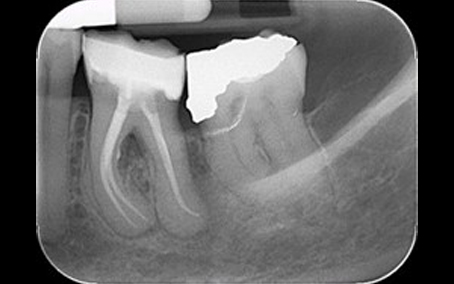

Pre Op Radiograph

Post Op Radiograph